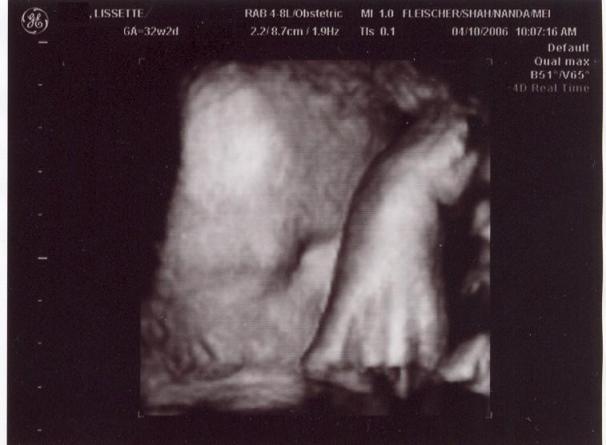

Damn paparrazzi!

This is what happens when u bother ur baby for a 4D Sono! The baby was with it's hands away from it's face for 99% of the sonogram, and the moment we want a face shot, he/she puts it's arm in front of it's face...

Aww I'm sorry! But you got to she the baby's little face (side of it ) and hand!